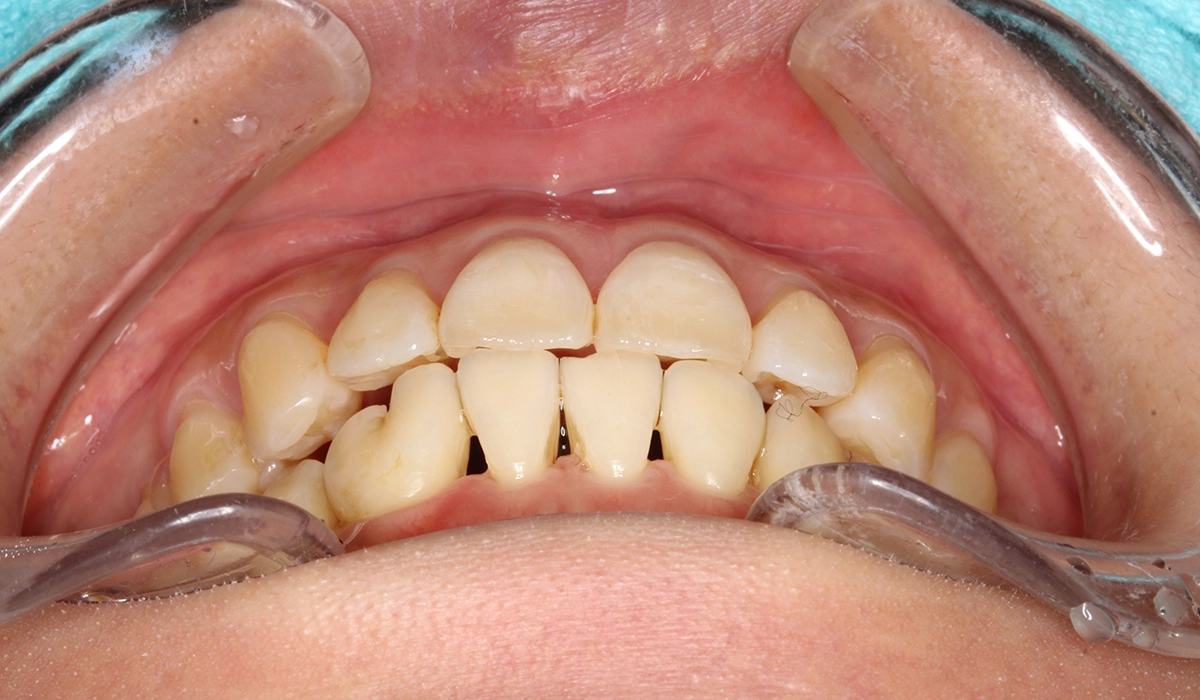

術前:前歯部

術後:前歯部